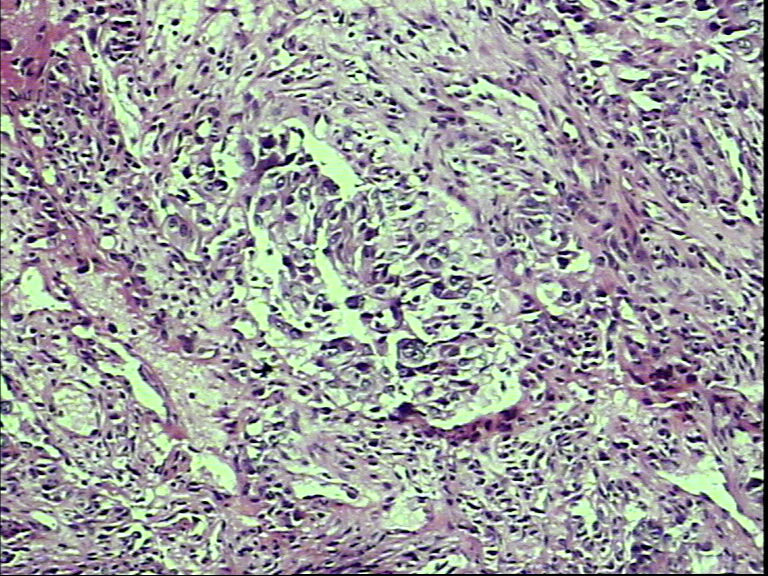

支气管活检,女性,65岁

• 支气管活检,女性,65岁图1

• 支气管活检,女性,65岁图2

• 支气管活检,女性,65岁图3

• 支气管活检,女性,65岁图4

• 支气管活检,女性,65岁图5

• 支气管活检,女性,65岁图6

• 支气管活检,女性,65岁图7

组织太少,考虑鳞癌(建议再检)。

鳞状细胞癌

就本例而言基本肯定是鳞状细胞癌,退一步讲是腺癌的话,也不需再次活检了,排除小细胞癌了,不影响治疗方案了,只要其他情况还好的话,手术治疗是首选了。

图片质量太差 需排除腺鳞癌

鳞癌?腺癌?